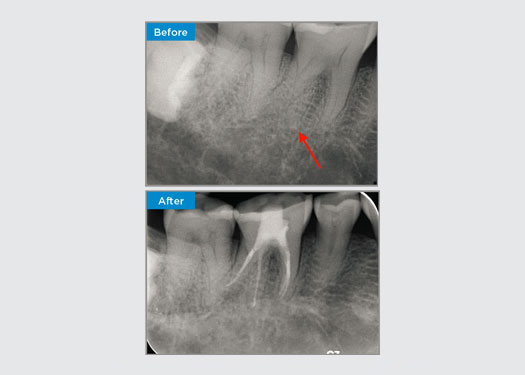

Le patient s’est présenté avec une pulpite irréversible sur la dent 46. Sur la radiographie préopératoire, la dent 46 présente une racine distale supplémentaire (morphologie de la dent Radix Entromolaris). Un balayage CBCT a confirmé la présence d’une racine DL avec une courbure radiculaire sévère. Une sélection minutieuse des limes est essentielle pour cette racine DB délicate.

Dr Jack Lin, Endodontiste, Sydney, NSW Australie

Dans cette situation, la préservation de la structure de la dent/racine est essentielle pour réduire le risque de déviation, de déplacement, de fermeture, de perforation et de fracture de la racine. La sélection des cas, le diagnostic et la planification du traitement préalable sont importants. Le choix de la lime endodontique en fonction de sa flexibilité, de son efficacité et du respect de l’anatomie naturelle de la racine est essentiel.